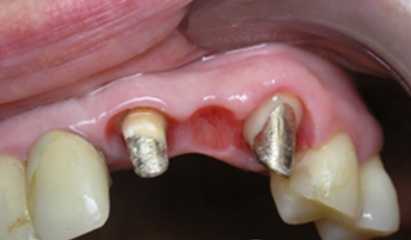

Протезирование

Когда вкладка готова, на нее может быть установлена коронка. Если речь идет о передней части зубного ряда и коронке из керамики или диоксида циркония, вкладка должна быть светлой. Коронки из этих материалов максимально приближены по внешнему виду к натуральным зубам. В том числе имеют нужный уровень прозрачности. Металлическая культевая вкладка будет просвечивать через слой керамики. Поэтому важно, чтобы опора соответствовала требованиям эстетики. Может быть использована композитная культя на основе штифта или внутрикорневая культевая вкладка из диоксида циркония.

Для протезирования жевательных зубов прочность гораздо важнее эстетики. В этой области часто применяется металлокерамика, для которой не важен цвет культи и главную роль играет ее способность выдерживать нагрузки. Когда культя готова, с челюсти снимается слепок для изготовления модели. По этой модели в дальнейшем изготавливается коронка.